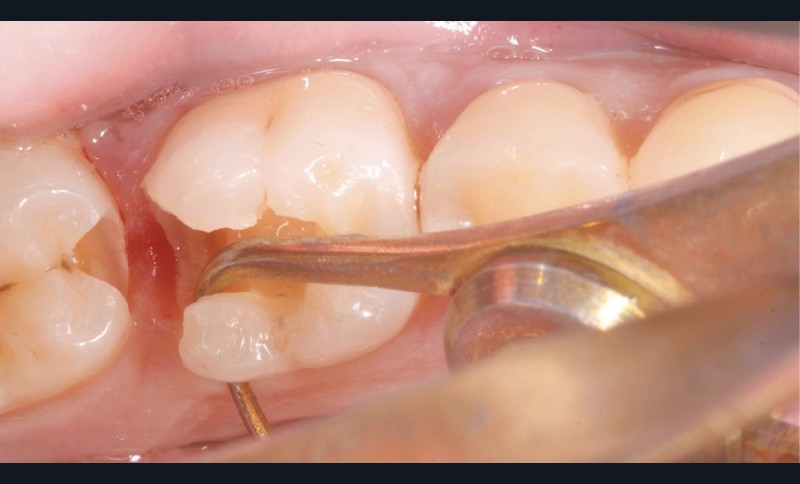

Lors de la préparation d’une cavité pour inlay/onlay, il est fréquent d’être confronté, en fin de nettoyage, à la présence d’une ou plusieurs parois résiduelles dont la résistance mécanique paraît douteuse du fait de leur localisation ou de leur épaisseur. Les parois épaisses (+ de 2 mm) peuvent généralement être conservées (cas clinique 1) et les parois fines (- de 1 mm) doivent généralement être recouvertes. Un inlay (en composite ou en céramique) est alors réalisé. Il doit avoir lui même, au final, une épaisseur globale minimale de 2 mm pour assurer sa résistance mécanique intrinsèque à la mastication. Si un recouvrement cuspidien est indiqué, la réduction occlusale doit donc se faire sur 2 mm de hauteur au minimum [1, 2].

Mais qu’en est-il des parois résiduelles d’épaisseur intermédiaire (entre 1 et 2 mm) (cas clinique 2) ?